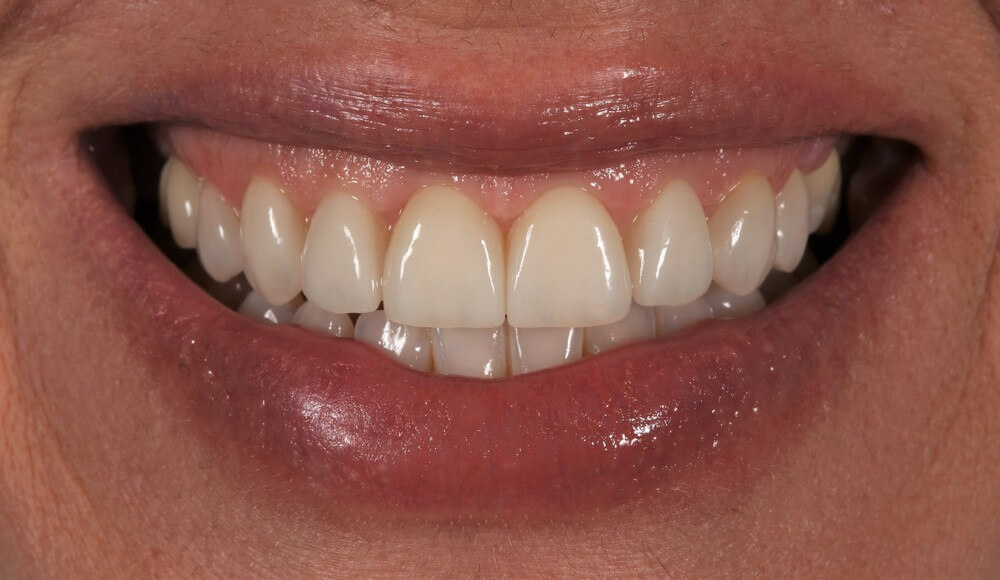

Μετά